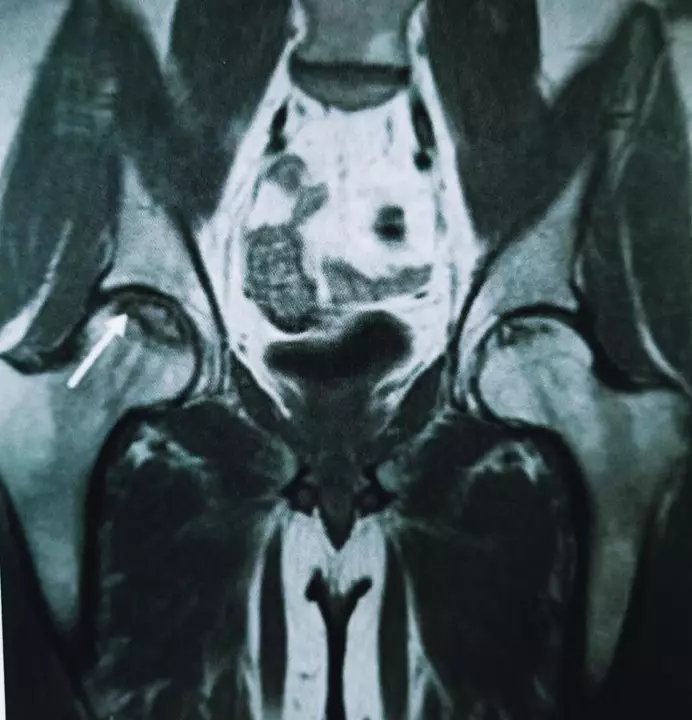

通过解读《新冠肺炎诊疗方案》第六版,我们可以得出,此次抗击新冠肺炎,只是对于重型、危重型出现呼吸窘迫综合症的患者,需要大剂量激素治疗以稳定病情,但对激素的使用剂量及时间提出明确要求,而非“尽早、大剂量、长时间使用激素”,所以此次战“疫”过后,理论上股骨头坏死的发生率应该低于非典时期。但也需要疫情结束后进一步验证。对于需要大剂量激素治疗的患者,病情改善或稳定后,要及时调整激素剂量或停药。激素治疗期间应注意预防股骨头坏死,建议应用改善微循环药物,口服降脂药、二磷酸盐、维生素D及钙片。对出现关节疼痛的患者,尤其是髋关节前方腹股沟区疼痛,应及时进行MRI检查,早发现,早拄拐,早治疗,可口服前列环素类药物、抗凝药、降脂药、二磷酸盐,配合高压氧、冲击波等非手术治疗。若股骨头坏死非手术治疗效果不佳,股骨头塌陷前(MRI提示股骨头坏死系I/II期-图4)可以行保髋治疗,包括:髓芯减压术、植骨术和截骨术(图5-7),其中髓芯减压和植骨术可通过微创手术完成。但一旦X线出现新月征(III期-图8)及股骨头塌陷、变形(IV期-图9),最终只能行髋关节置换手术(图10)。

图5 股骨头坏死早期行髓芯减压术示意图

图6 股骨头坏死早期行髓芯减压自体腓骨植入示意图